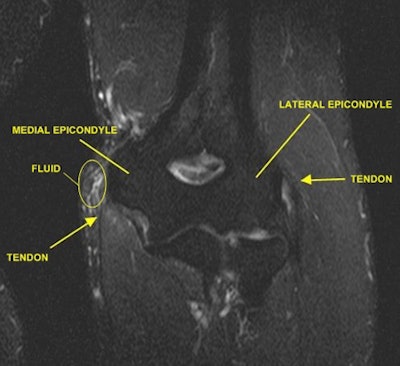

"We always hear about these injuries, but we really have no idea what they look like," Lalaji said. "We can only associate to them by, 'Yes, I know that is a knee.' If I can give people a snapshot or a little snippet of what [an injury] looks like and what normal looks like, the next time they hear about that injury they automatically can visualize [it]. "

Just to be clear, the clinical images posted on the website are not of the athletes. If the pictures were the athletes' actual images, it would be an obvious HIPAA violation. In fact, InsideInjuries.com specifically states that the images are only examples of the injury the athlete incurred, based on media reports.

"It is sort of a general diagnosis of the injury," Lalaji said. "It may be something like a hip sprain, which could be a hip flexor or something else. There are two or three different possibilities" posted on the site for an athlete's reported injury.

While the posted images are not detailed enough to be used as an educational tool for current or would-be radiologists, the site might be useful for an internist, family practitioner, or other healthcare specialist who is not in the field of imaging, Lalaji said.

"They may not know what some of these injuries look like," he added. "I think people outside of the field of radiology or orthopedic surgery might benefit from the site as a teaching tool."